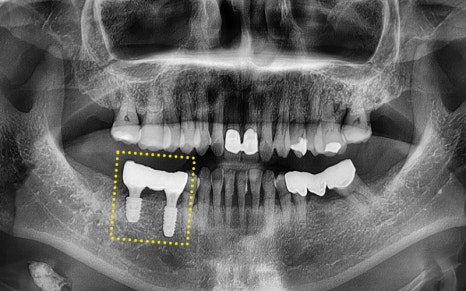

We waited 충분히 long so that the implant could be well fixed in the jawbone,

![[Seokchon Gobun Station Dental Clinic] When Is an Implant Needed? image 6](https://pub-9f2bb3498faf4d1d8714b41df24753e3.r2.dev/content/clinics/archive/2yawovf9te/naver_blog/qkrgnsdms66403/assets/by_hash/b57510d3c14833982a2fc39f3d71d9a77fe733bb2d292ef5af5631d2cc94fd2d.png)

This shows the custom abutment being attached

for the crown (prosthesis) work.